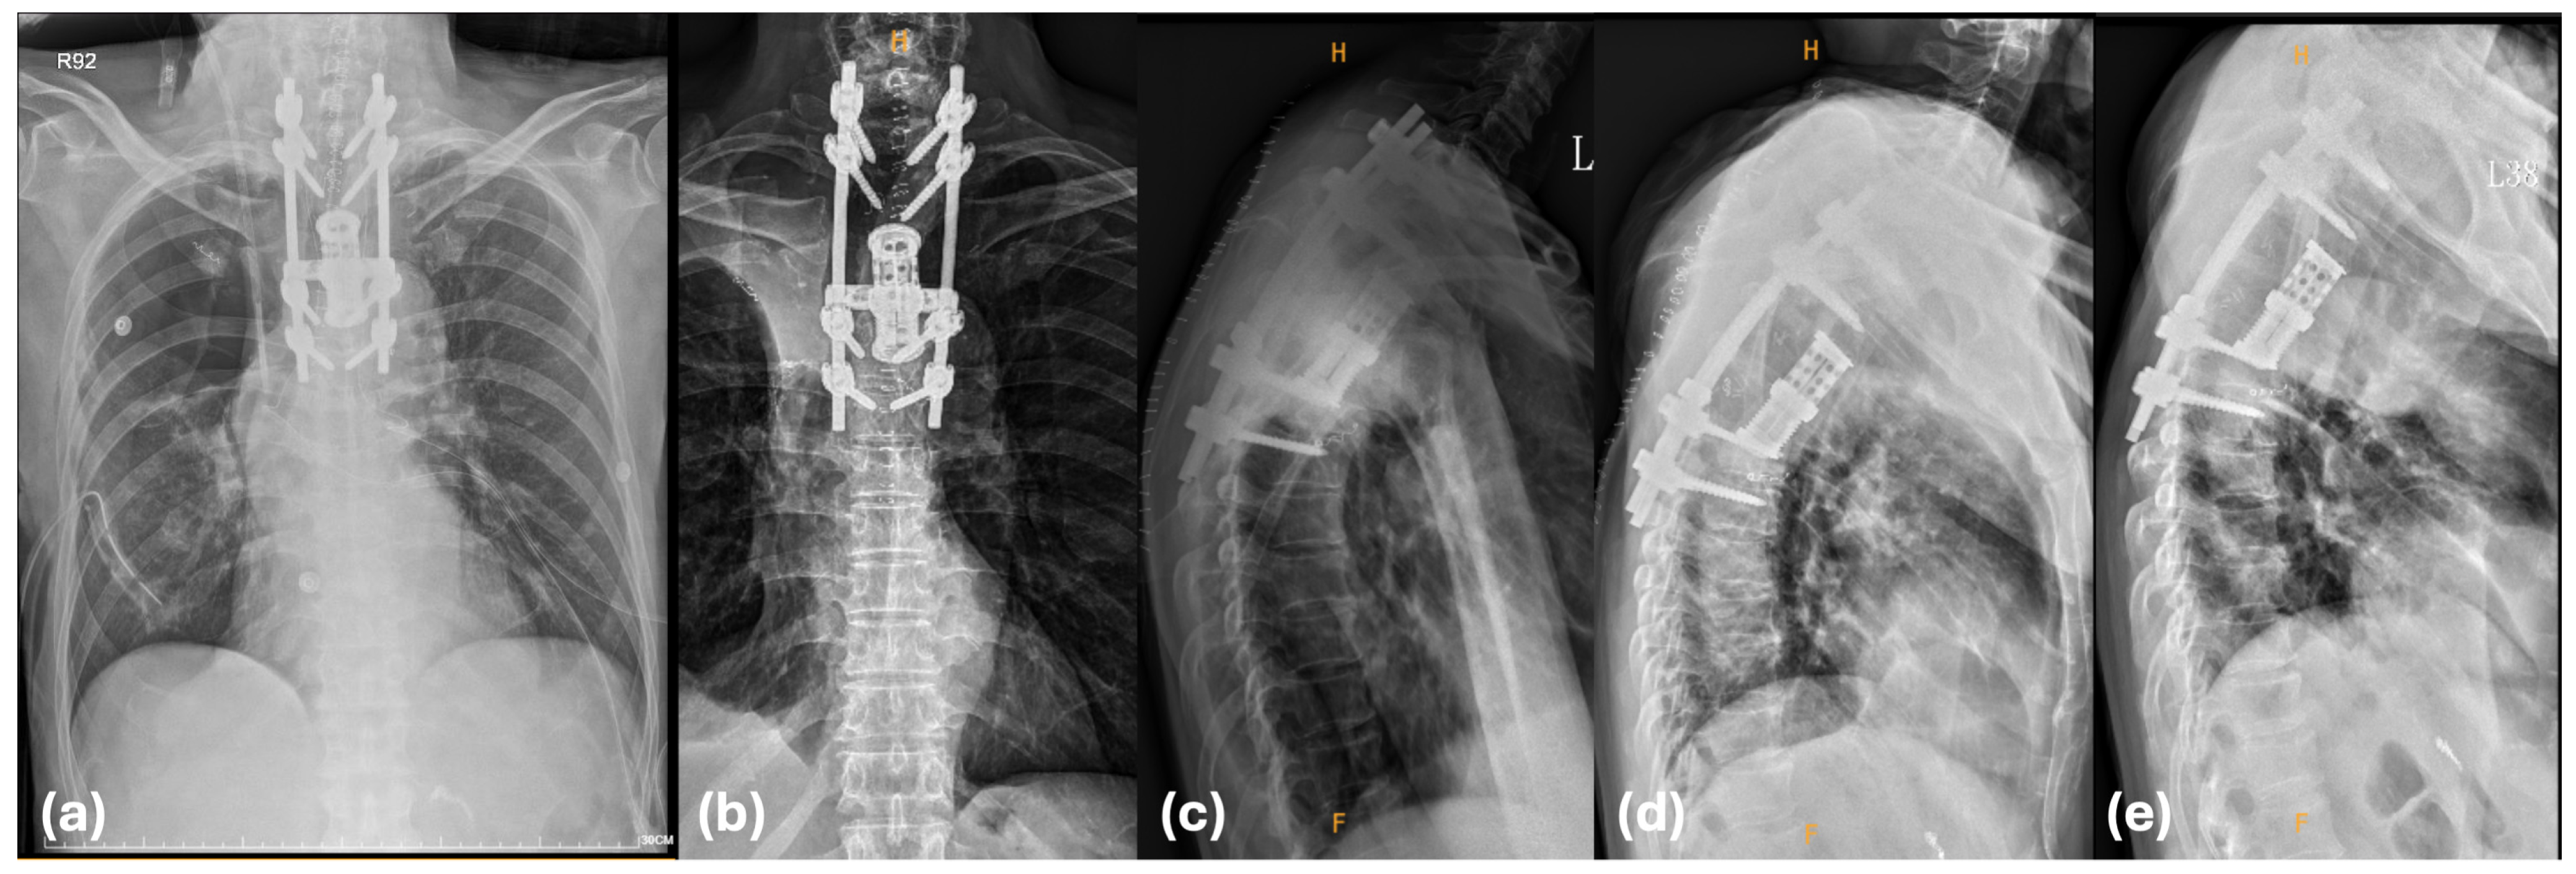

2.2.1. Stage 1: Posterior Spinal Release and Fixation

2.2.2. Stage 2: Thoracic Phase (VATS Lobectomy and Reconstruction)